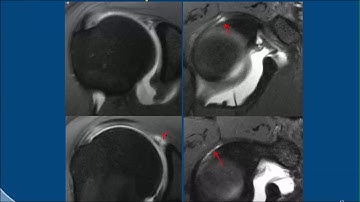

Shoulder Arthrography